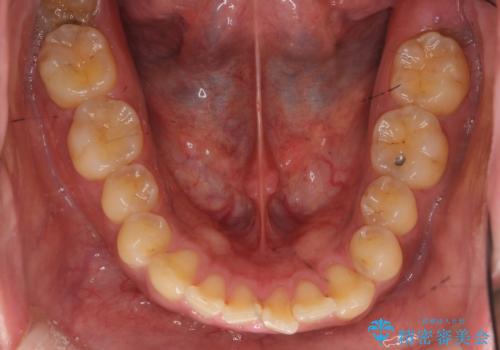

前歯のねじれを 1年かけずに矯正 インビザライン

- 前歯のねじれを主訴に来院。

インビザラインで治療しました。